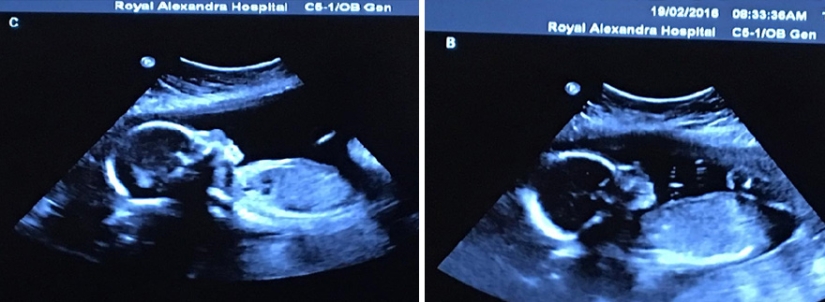

By Pictolic https://www.pictolic.com/article/photo-shoot-of-very-rare-and-absolutely-identical-quadruplets.htmlThe chance of having four children (not with the help of IVF) is one in 729 thousand. And as you can imagine, the chance of having four identical twins is even less. But one Canadian couple was lucky. Bethany and Tim Webb, we can say, did almost the impossible — in May of this year they had four lovely and absolutely identical daughters — Abigail, McKayla, Grace and Emily. And this happens in one case out of 15 million!